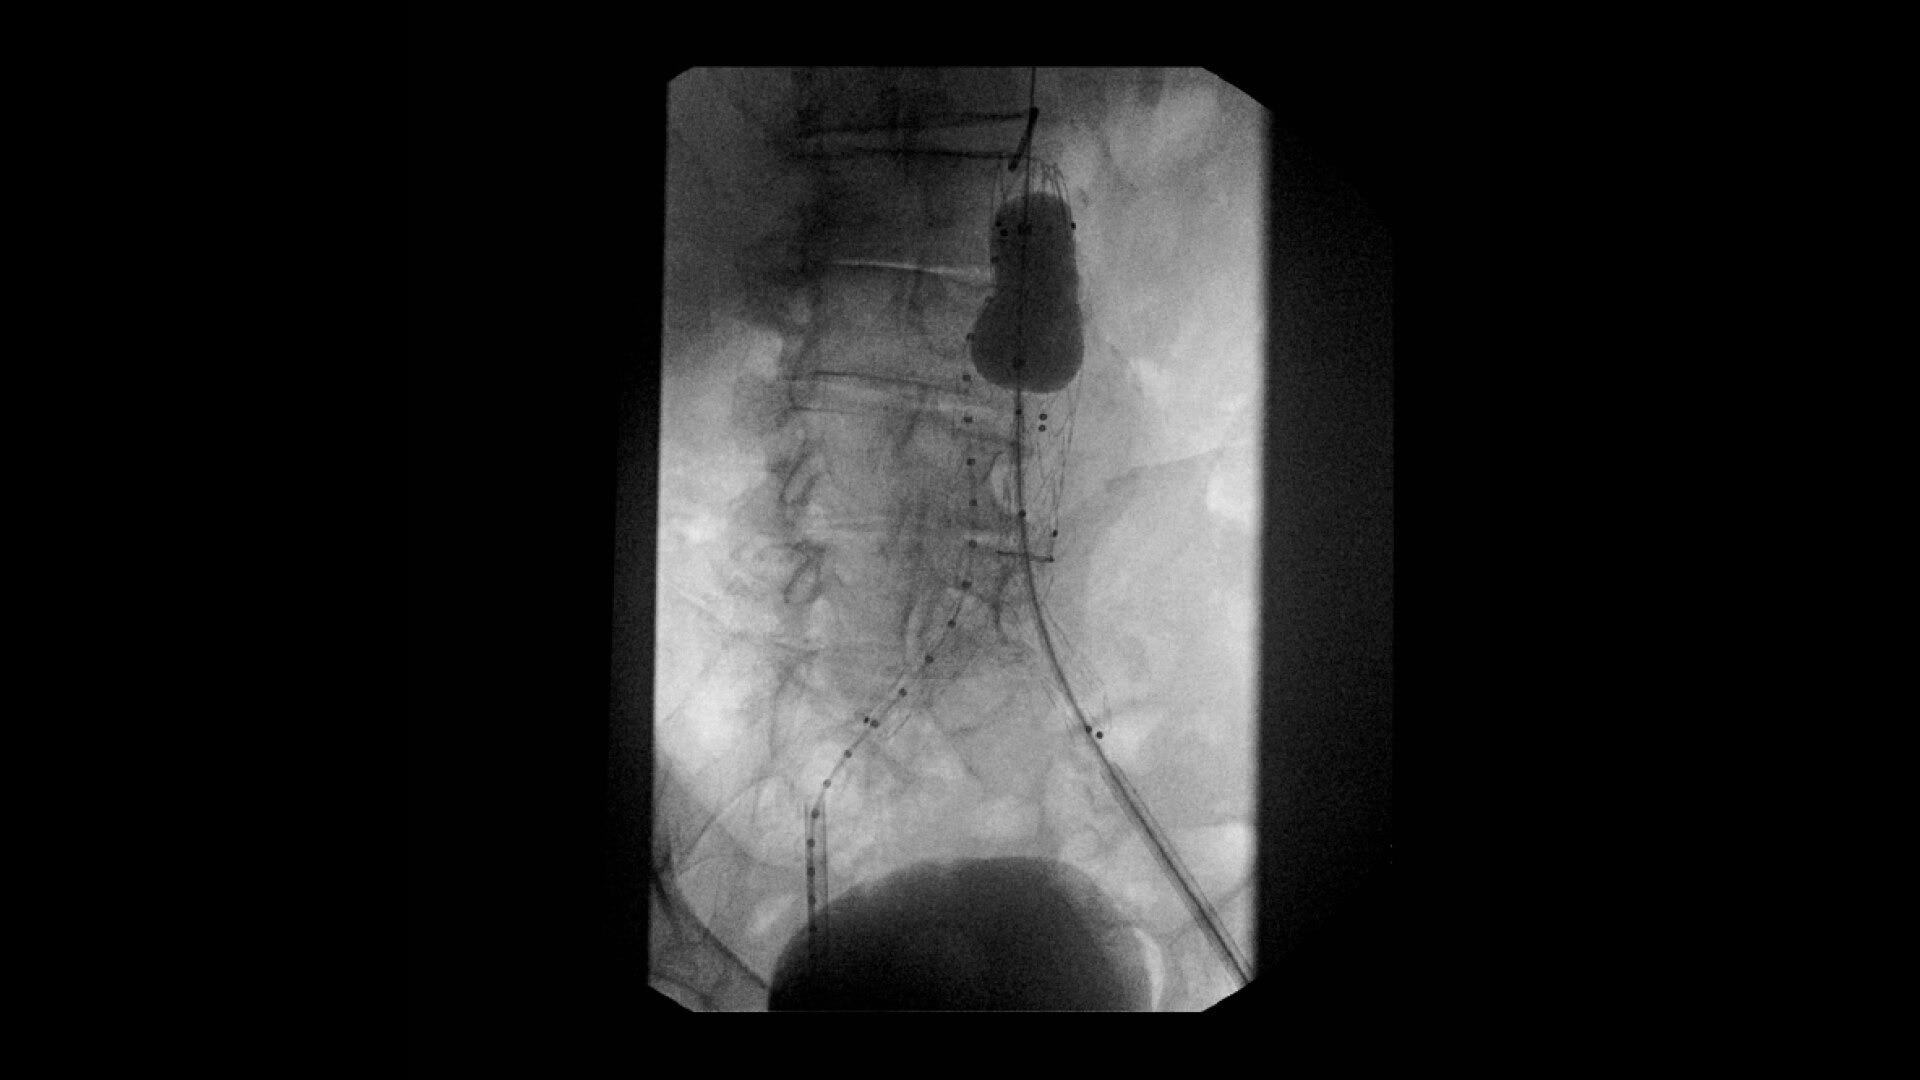

Complex vascular procedures require powerful imaging systems. OEC premium C-arms perform in a variety of procedures such as:

•Abdominal aortic aneurysm (AAA) stent and balloon deployment

• Infrarenal aortic aneurysm repair

• Recanalization and stent placement in iliac arteries